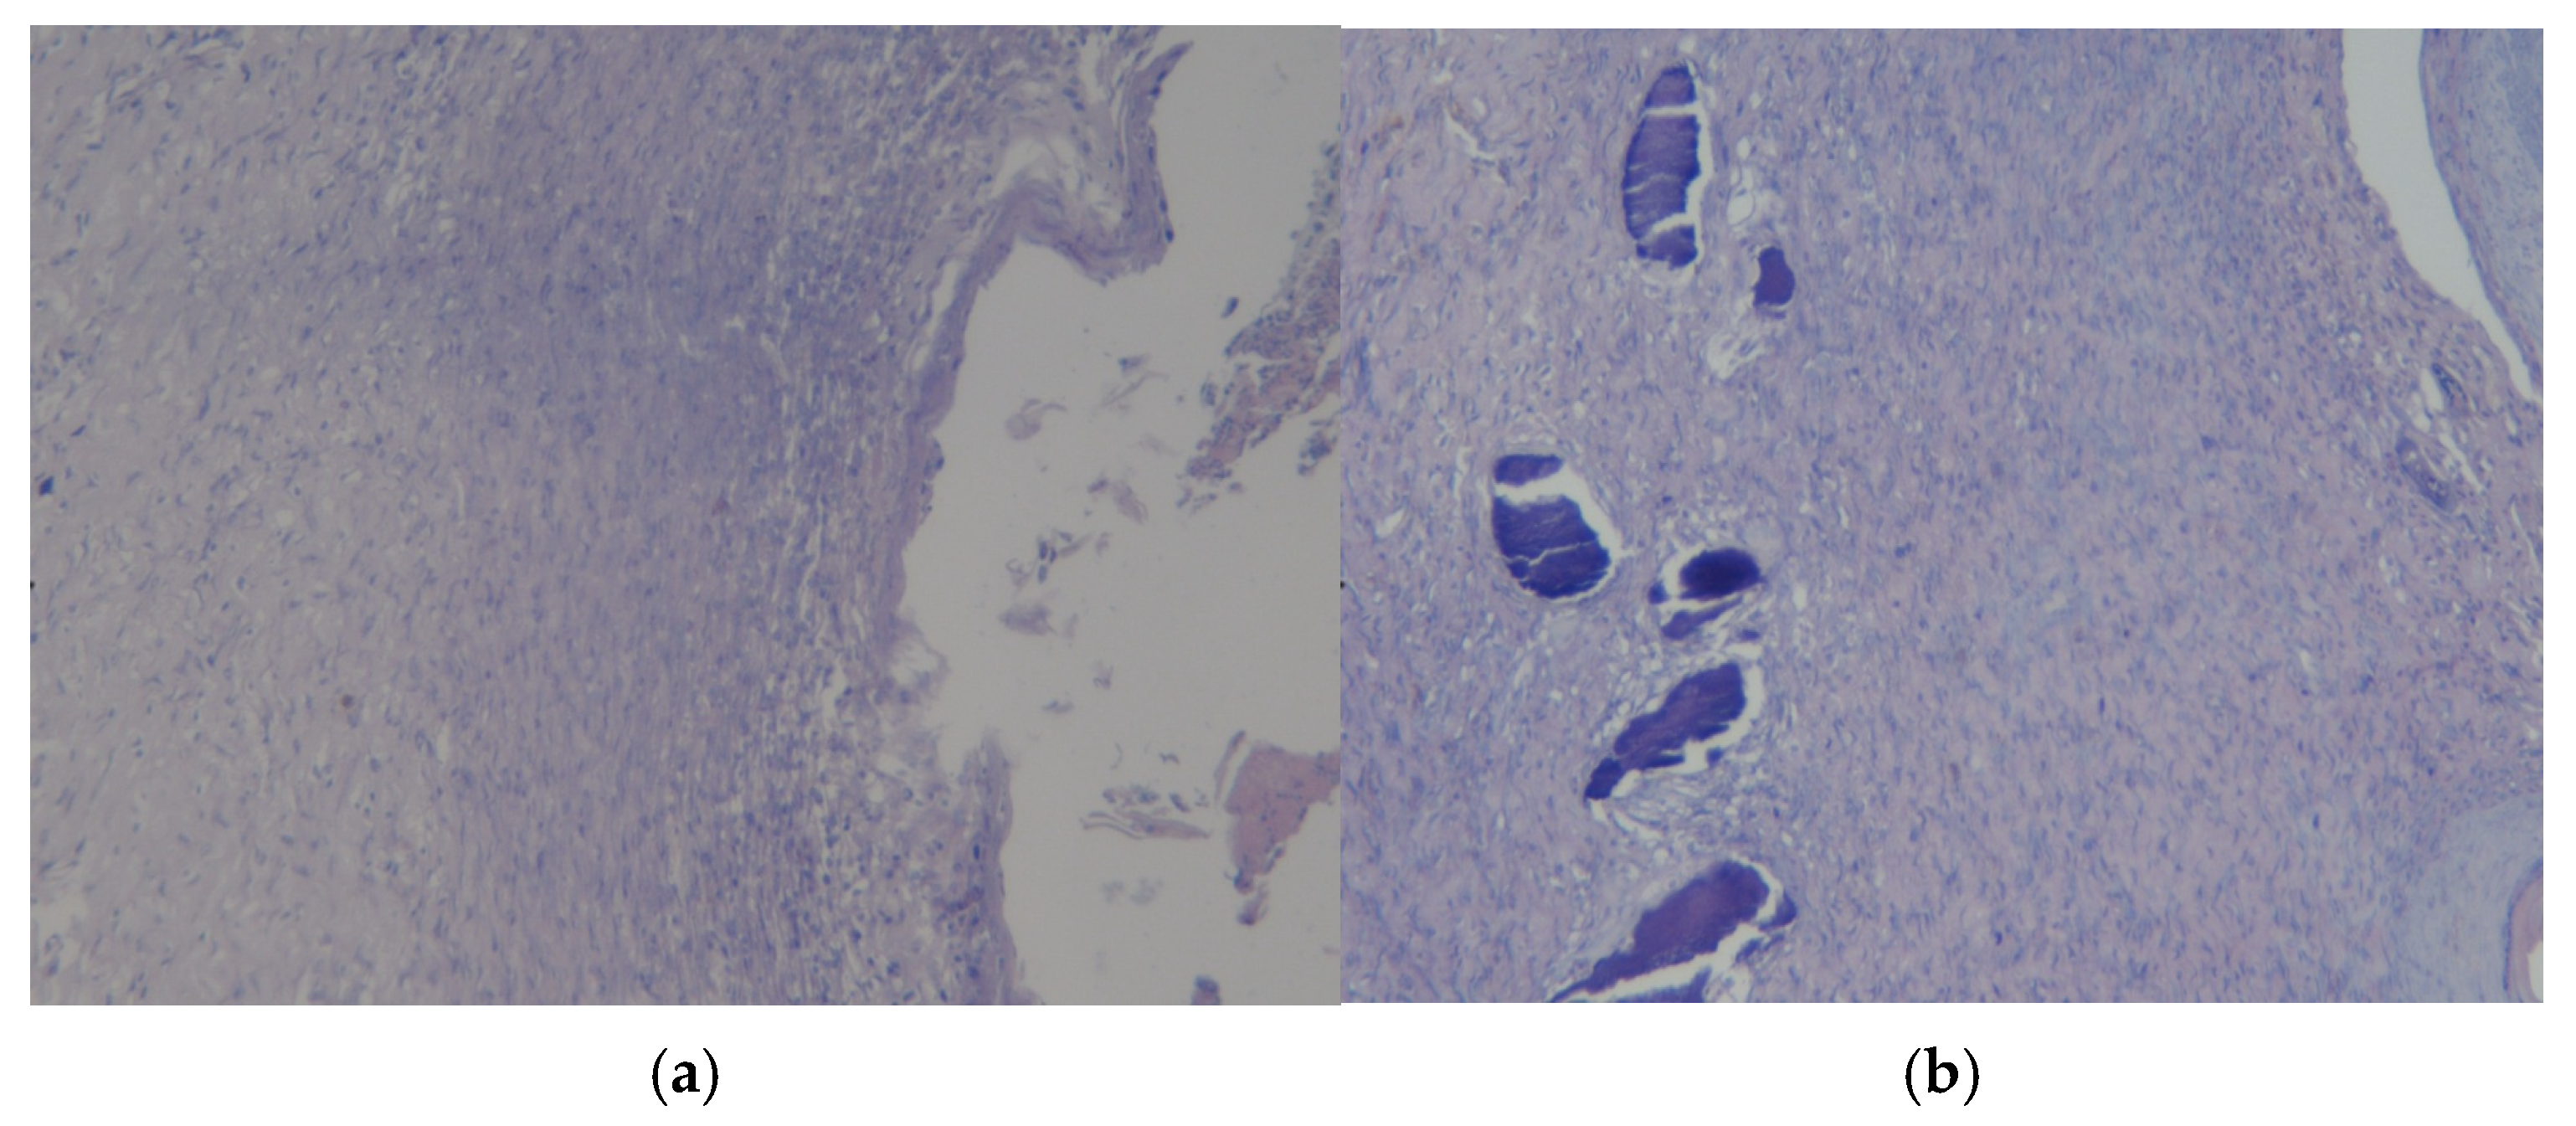

3.3. Results of Morphological Examination

3.4. Assessment of Microcirculation in the Healing Process of Burn Wounds